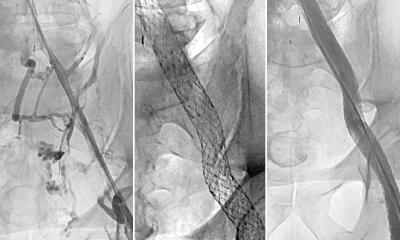

The study enrolled 225 patients at 29 sites across the U.S. who had been treated for deep vein thrombosis for at least 3 months and had blockage of the iliac vein (a major vein in the pelvis) causing substantial disability. Patients were chosen at random to receive either a stent — a mesh tube inserted into the vein to reinforce and expand it — plus standard treatment with compression and blood-thinning medications, or standard treatment alone. A stent is placed in a two-to-three-hour operation that requires only tiny incisions.

At the start of the study, 93% of participants met the clinical criteria for severe post-thrombotic syndrome. Six months after treatment, just 40% of patients who received the stent still experienced severe post-thrombotic syndrome, compared to 61% in the standard care group.

Patients with stents also reported improved symptoms in the veins of their legs and overall quality of life following the procedure compared with those on standard treatment. On a 100-point quality of life scale, those who received the stent scored 14 points higher, a large improvement.